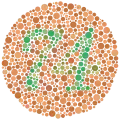

| •Colour vision: | to test colour vision |

| ••Ishihara's chart | to determine the type of colour blindness |

A set of lenses used in refraction testing Ishihara Plate 9

Ishihara Plate 9 Ishihara Plate 23